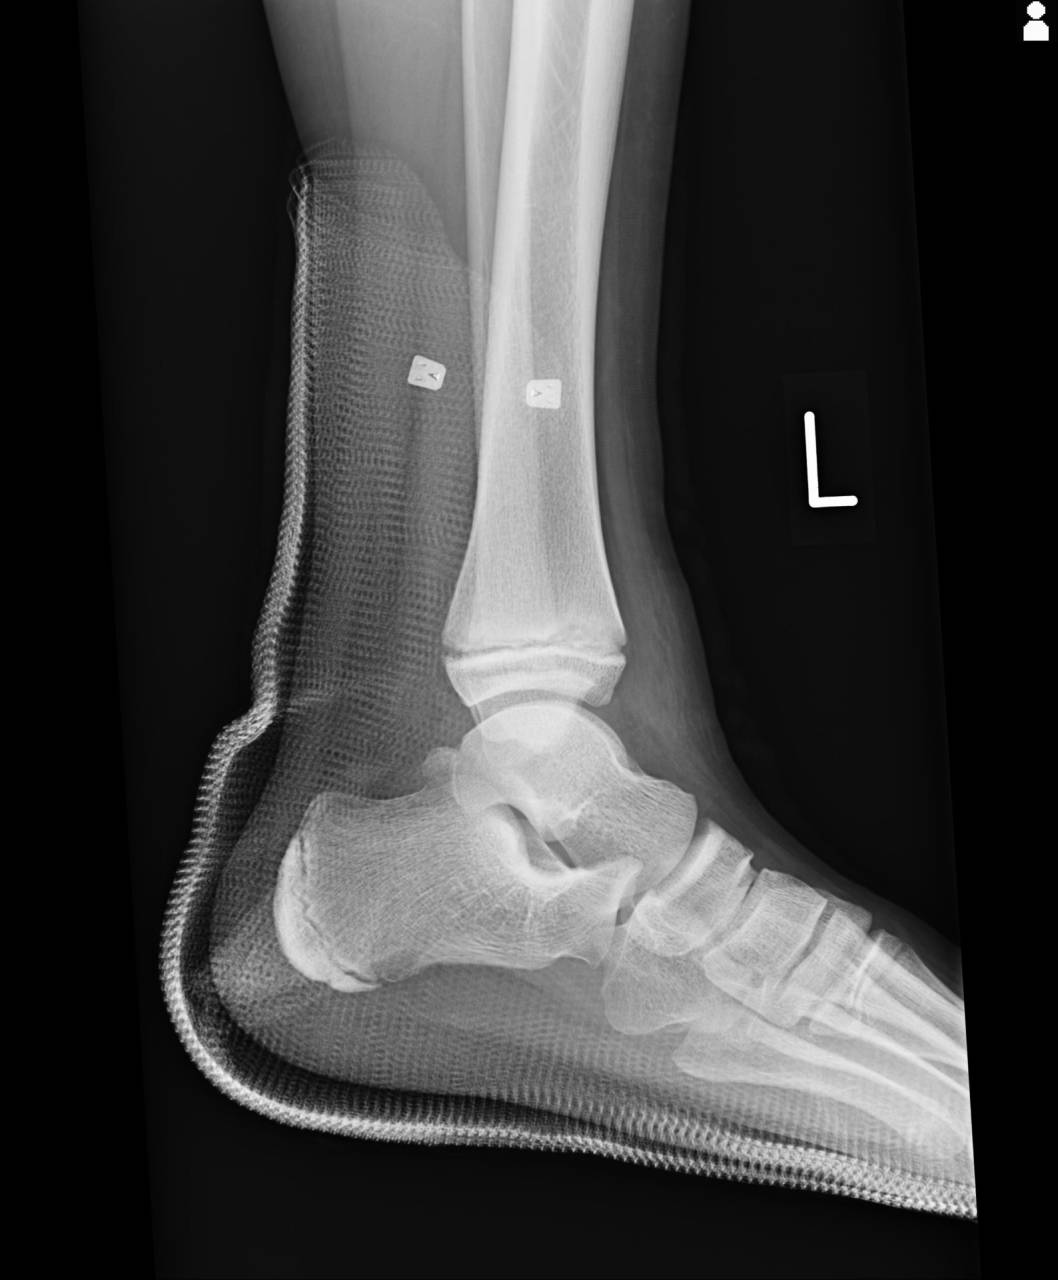

痛みが骨組織にあることから骨折の疑いが濃厚だったため、超音波観察装置(エコー)にて組織の損度合いの確認を行った所、圧痛のあった部位に骨折線があったので当整骨院が提携している病院にてレントゲン検査を依頼しました。

撮影した画像を確認すると腓骨骨端線部と脛骨骨端線部周囲部に骨折が認められ骨折として施術をしていきます。

施術はレントゲン撮影前に距骨亜脱臼を整復していて、亜脱臼はキレイに整復されていて、骨折部には微弱電流にて骨の組織修復を行います。